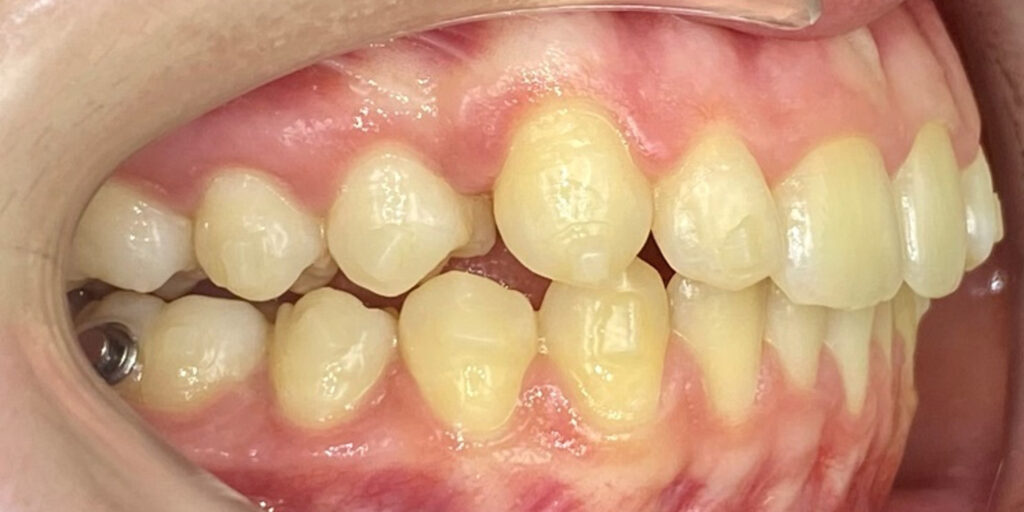

The 14-year-old female patient visited the orthodontic practice in February 2021. The chief complaint was that her upper arch was affecting her confidence in her smile. Upon examination, the patient was found to have a normodivergent facial pattern and a skeletal class II with mandibular retrusion. An intraoral examination revealed narrow arches, a class II molar and canine relationship, deep bite, retroclined upper and lower incisors, and retained teeth 63, 74, and 84.

After undergoing maxillary expansion, Dr. Sorina Blaj assessed the patient again in September 2021, and at that point, tooth 84 had exfoliated, tooth 44 had erupted, and tooth 23 had started to erupt.

After considering that 23 no longer needed to be surgically exposed, Dr. Blaj, the patient, and her parents decided to use Spark Clear Aligners to correct dental issues. The treatment began in November 2021, utilizing the 3D Approver Software™ to design a digital plan. The plan aims to:

The treatment includes sequential distalization of the maxillary teeth and mesialization of 3.6, virtual extraction of 74, composite attachments on all distalizing teeth, class II elastics, bite ramps on upper central incisors, IPR and eruption guides for teeth 23 and 35.